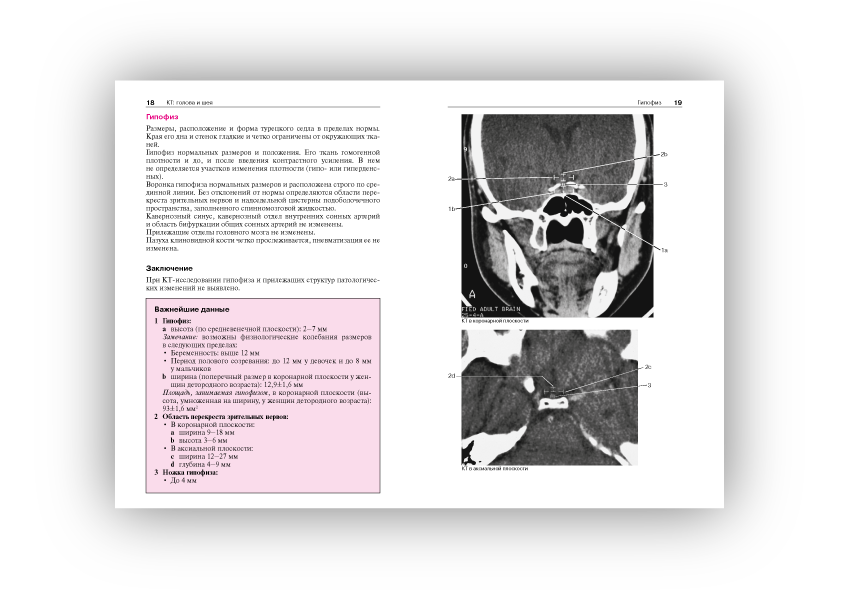

Норма при КТ- и МРТ-исследованиях: пер. с англ./ Торстен Б. Мёллер, Эмиль Райф; под общ. ред. Г.Е.Труфанова, Н.В.Марченко.- 3-е изд. - М.: МЕДпресс-информ, 2016. - 255, [1] с.: ил..

Широкое использование в современной клинической практике компьютерной томографии и магнитно-резонансной томографии как решающих методов диагностики при многих болезнях, относящихся к различным клиническим специальностям и разным анатомическим областям, выдвигает на первый план проблему границ между нормой и патологией при трактовке изображения на срезах.

Помочь врачу - специалисту, составляющему заключение на основании анализа изображений, полученных при КТ- и МРТ-исследованиях, - основная задача этой книги, которая как бы продолжает ранее вышедшую книгу Норма при рентгенологических исследованиях. Каждому из названных методов посвящен самостоятельный ее раздел, охватывающий все исследуемые анатомические области (голова и шея, грудная клетка и т.д.).